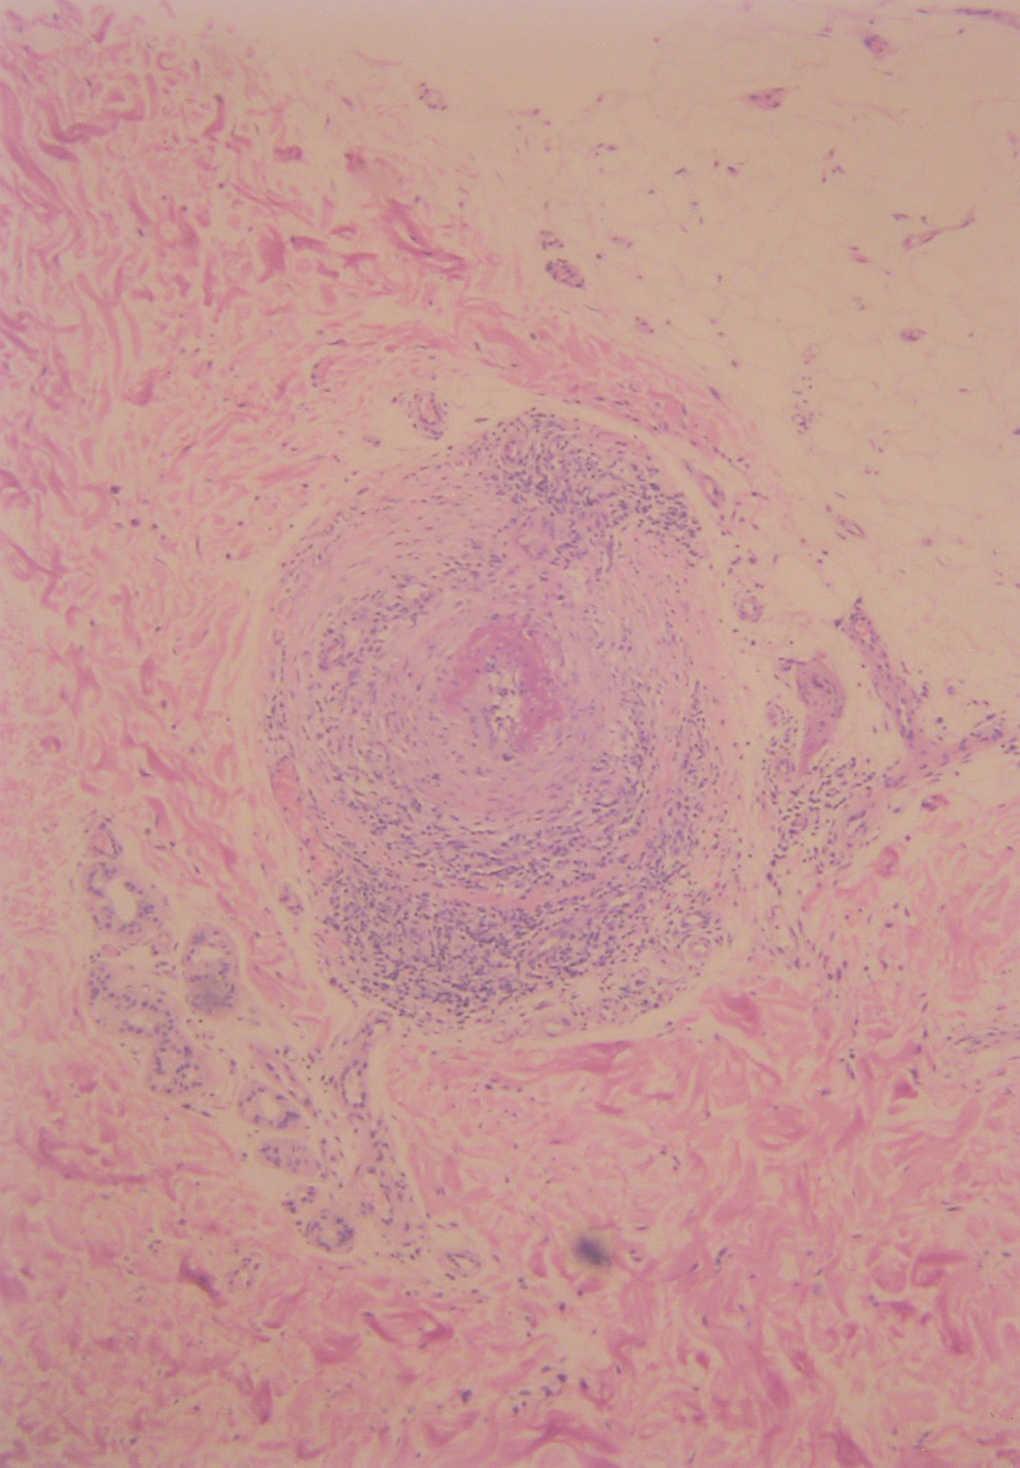

Fig. 4.--Detalle histológico de la arteritis con infiltración linfocitaria. (Hematoxilina-eosina, x40.)

En la biopsia cutánea se apreciaba una arteria de mediano calibre en la porción inferior de la dermis reticular, con un infiltrado predominantemente linfocitario dispuesto entre y alrededor de las capas de la arteria. La arteria presentaba signos de necrosis fibrinoide (figs. 3 y 4).